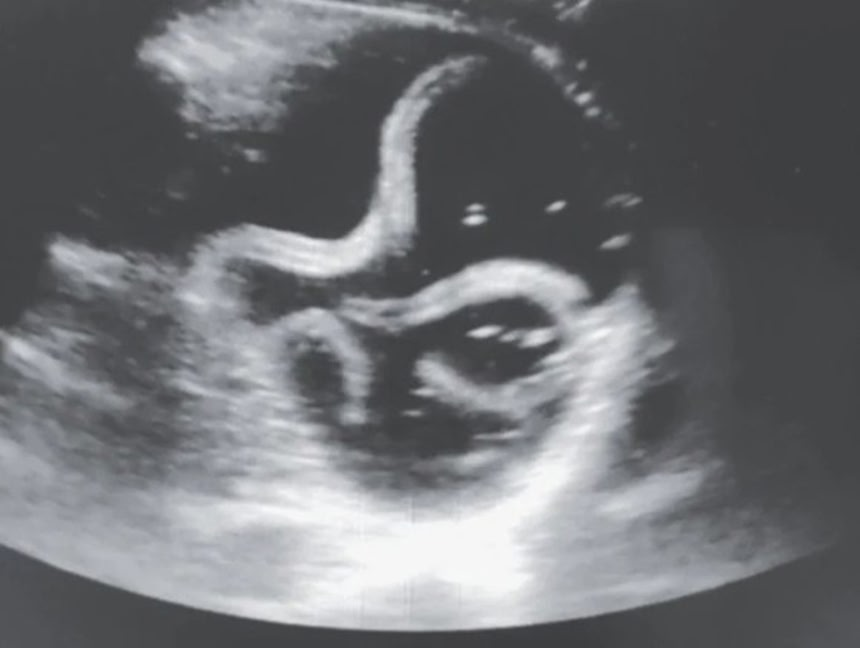

続きを読む超音波(エコー)検査は超音波を対象物に当ててその反響を映像化する画像検査法だ…